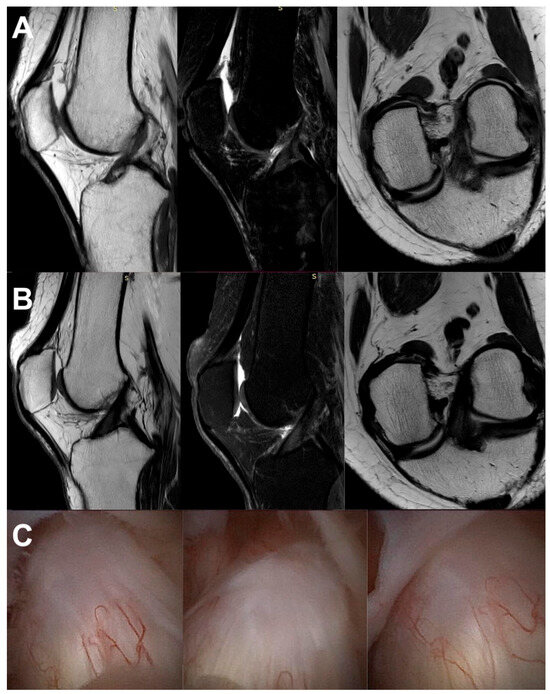

2.4. Imaging Examination

3.3. Imaging Analysis